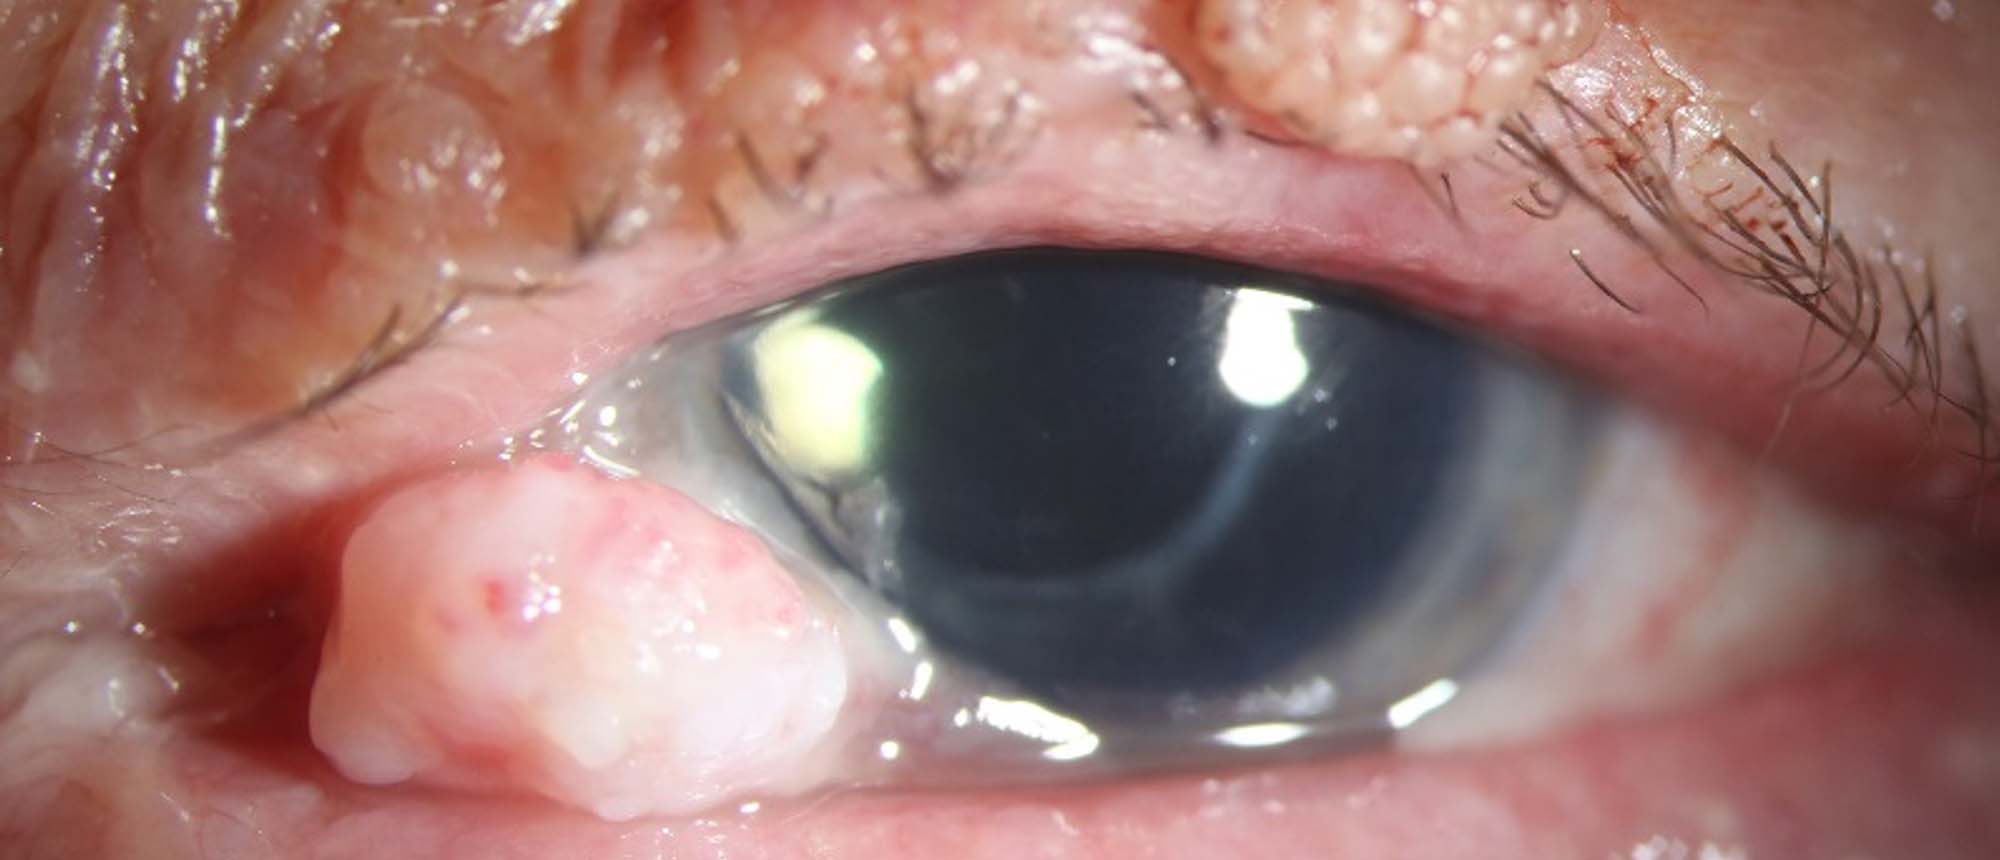

Nontuberculous Mycobacteria Keratitis

Abstract A patient five months after bilateral simultaneous cataract surgery in another country presents to the BPEI emergency room with bilateral decreased vision and extreme right eye pain for the last 2 weeks. Their exam was notable for visual acuity of hand motion in the right eye and 20/150 in…